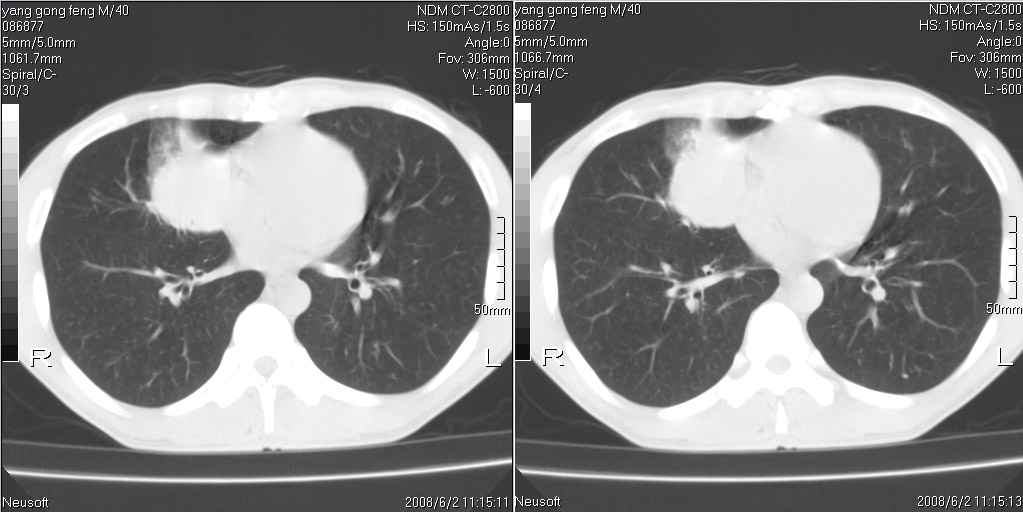

标题: CT15138:男,40,咳嗽胸痛. [打印本页]

标题: CT15138:男,40,咳嗽胸痛.

外院穿刺未见癌细泡,结核菌素实验阳性,未正规治疗2个月复查病灶及纵隔淋巴结增大

考虑周围型肺癌可能性大

考虑周围型肺癌可能性大!

考虑右肺中叶周围型肺癌并纵隔淋巴结转移。

考虑周围型肺癌伴纵膈淋巴结转移可能性大